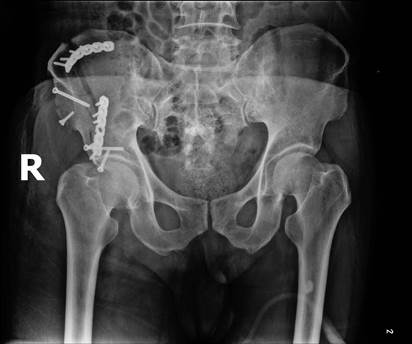

病例三:Tile B1分型,术后复查X线